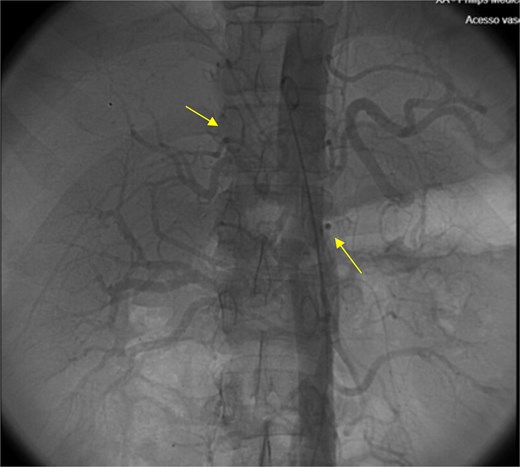

The patient presented at our Emergency Department with a sudden, diffuse, intense abdominal pain. Upon physical examination, the patient’s blood pressure was measured at 132/76 mmHg, heart rate of 103 bpm and a temperature of 39.4°C. The abdominal examination showed a rigid abdomen, with diffuse tenderness, suggesting an acute abdomen scenario. Laboratory tests revealed elevated inflammatory parameters. A abdominal and pelvic computed tomography scan revealed pneumoperitoneum and free fluid in the right iliac fossa and pelvis (Fig. 1). An exploratory laparotomy was proposed and the intraoperative findings included a sigmoid colon perforation with faecal peritonitis. They proceed with sigmoidectomy and temporary abdominal closure, planning for a reintervention to restore gastrointestinal continuity. This was done, after 48 h, through mechanical latero-lateral colo-colic anastomosis. The histopathological examination confirmed diverticulosis with perforation. The patient was subsequently transferred to the intensive care unit, for 5 days. Posteriorly, he developed severe left lumbar pain and hypertension unresponsive to medication. A CT scan revealed left kidney acute ischemia due to left renal artery thrombosis (Fig. 2). Broad-spectrum antibiotic therapy and anticoagulation, was initiated, after assessment by the Vascular Surgery and Urology teams. During his hospitalization, the patient experienced additional thrombotic events, such as occlusion of the left radial artery, and right lower lobar pulmonary embolism. A workup for prothrombotic conditions was conducted, including tests for thrombophilia, lupus, cardiolipins, antinuclear antibody, total protein test, and immunoglobulins, all of which were negative. An angiography of the abdominal aorta revealed arterial microaneurysms in the splanchnic territories: hepatic, perigastric and mesenteric arteries, suggesting polyarteritis nodosa (Fig. 3). Echocardiogram showed no abnormalities. The patient also underwent a study of the left shoulder due to repetitive pain complaints, with a suspected rupture of the rotator cuff. Electromyography excluded peripheral nerve damage. No other complications were reported. The patient was discharged on the 21st day after surgery, under anticoagulation therapy and steroids due to a suspected diagnosis of polyarteritis nodosa. Twenty-seven days after surgical intervention, the patient returned to the ED, presenting with abdominal pain in the lower quadrants and nausea. He was hemodynamically stable with abdominal pain and tenderness on the left flank and iliac fossa. Laboratory tests revealed leukocytosis and hyperlactacidemia. The CT scan reported free fluid, free gas bubbles adjacent to the sigmoid which had a concentric circular thickening of the wall, just distal to the previous anastomosis (Fig. 4). An exploratory laparotomy was performed, during which a large hematoma on the wall of the left colon was identified, with no apparent signs of perforation. A peritoneal lavage, drainage, and a derivative ileostomy were carried out. During the post-operative period the patient maintained a small volume of purulent discharge through the abdominal drain, with no abdominal tenderness. A reevaluation CT scan was performed, highlighting a regression of the hematoma of the colonic wall but raised suspicion of a low output fistula near the anastomosis. Since the patient maintained hemodynamic and analytical stability, he was discharged from the hospital with home care, including an abdominal drain, parenteral nutrition, empirical antibiotic therapy, and gradual reduction in the steroid dosage. The patient was referred to the ED, on Day 6, due to enteric drainage. An enterocutaneous fistula was diagnosed, and he was readmitted. He received 12 days of full-dose parenteral nutrition, which reduced the fistula output and improved his clinical and analytical status. Due to residual drainage volume and an analytical and imagiologic improvement, the drain was removed, and the patient was discharged, tolerating an oral diet, and with a functioning ileostomy.

Angiography of the abdominal aorta revealed arterial microaneurysms suggesting polyarteritis nodosa (arrows).